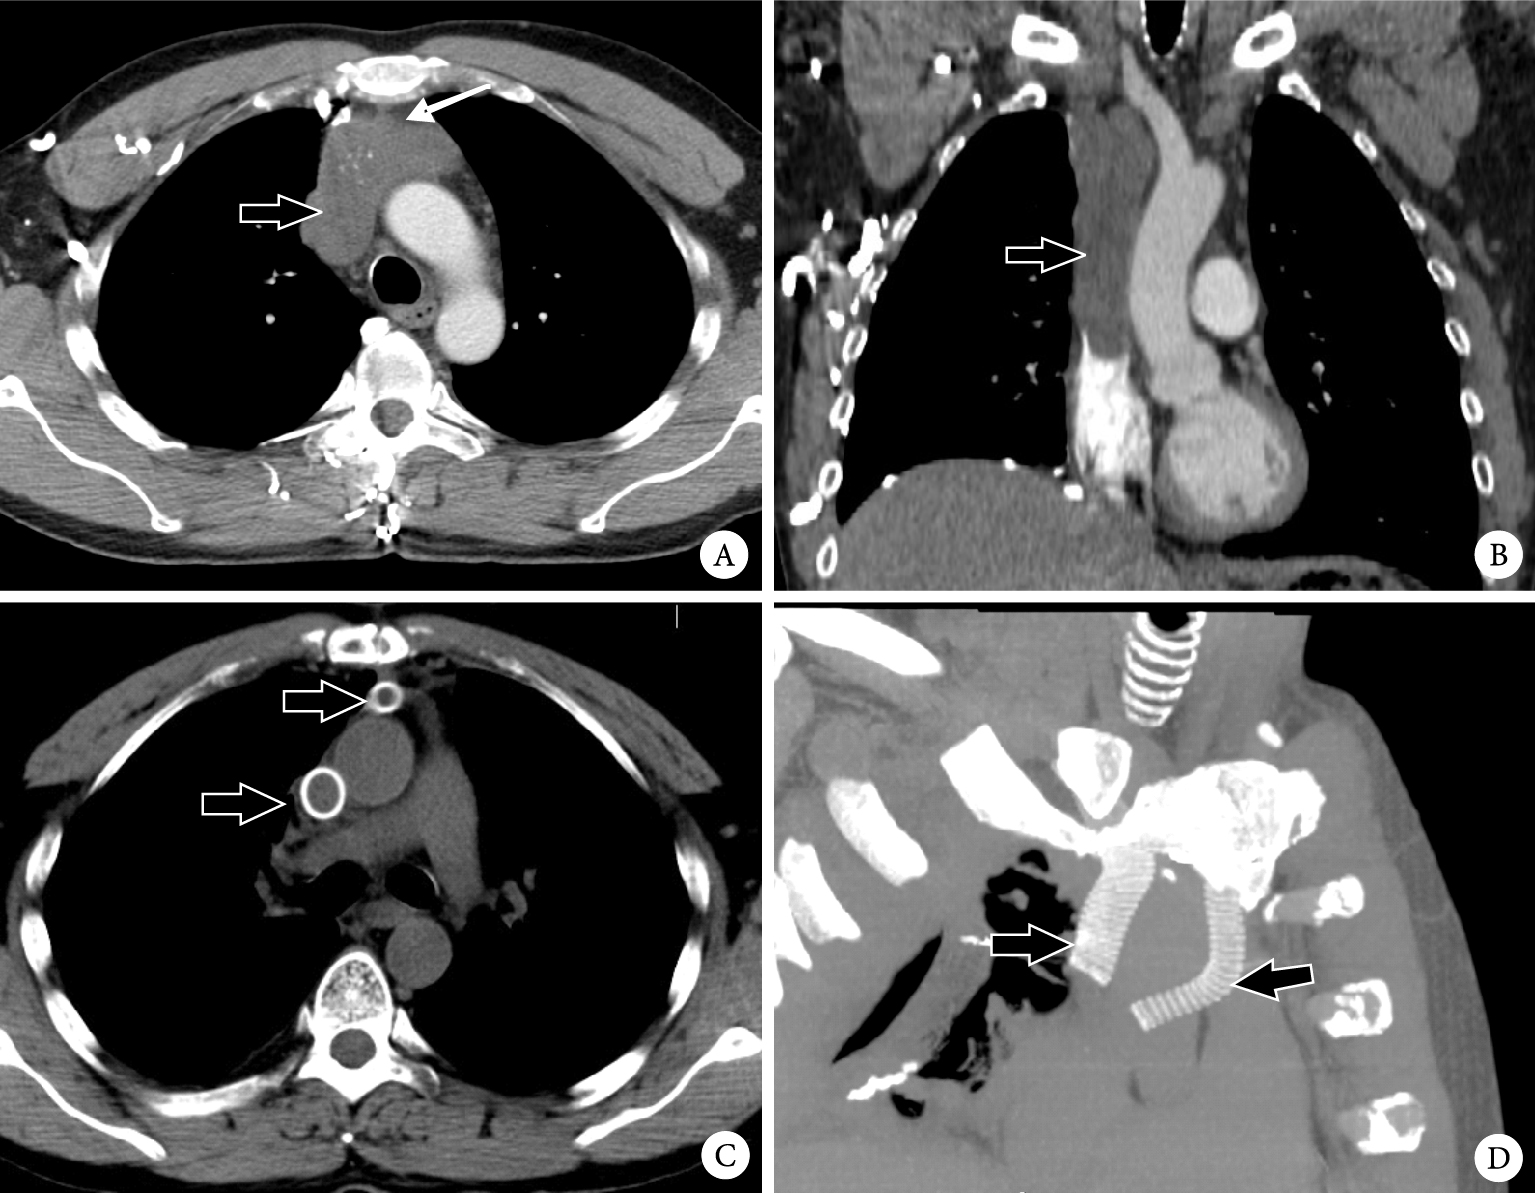

手術盡量完整切除腫瘤,累及心臟血管的處理包括:上腔靜脈+左無名靜脈人工血管置換+右無名靜脈、右心房切開取瘤栓+右房部分切除1例,為胸腺瘤B1型,術前行30 Gy放療縮小腫瘤并減輕上腔靜脈阻塞綜合征的癥狀后再行手術,見圖 1。

注:AB為術前CT,粗箭頭示上腔靜脈瘤栓完全栓塞,細箭頭示腫瘤阻塞左頭臂靜脈;CD為術后CT,粗箭頭示人工血管。